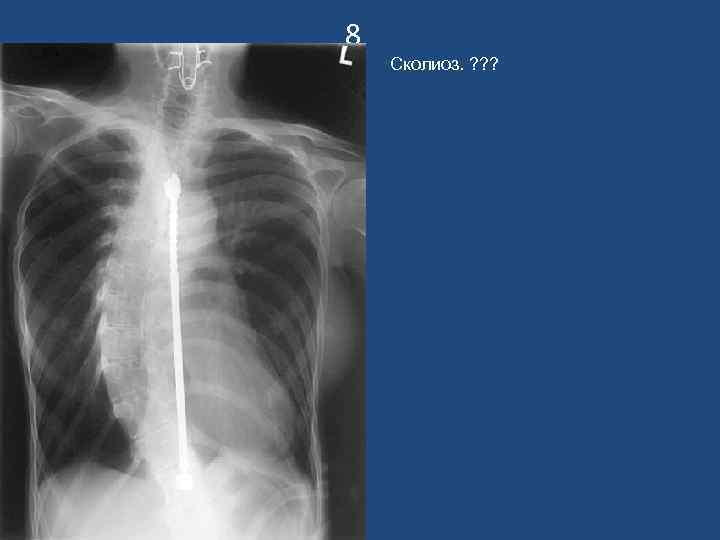

8 Сколиоз. ? ? ?